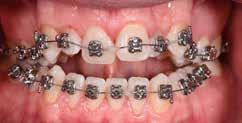

69 68 ESTETICA FUNZIONE POSTURA Valori cefalometrici iniziali ANB ANB 6,20 Posizione del Mascellare SNA 84,20 Posizione della Mandibola SNB 78,00 Angolo Articolare SArGo 132,00 Angolo Goniaco ArGoMe 134,00 Angolo incisivo inferiore Corpo Mandibolare liMand 97,00 Angolo incisivo superiore Base Cranica Anteriore IsCran 107,00 Angolo Interincisivo II 123,00